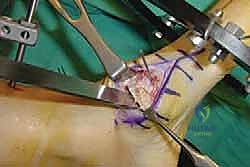

2. الشق الجراحي والوصول للمفاصل

يتم عمل شق جراحي واحد أو شقين (أحدهما في الجزء العلوي الداخلي والآخر في الجزء الخارجي) للوصول إلى مفاصل منتصف القدم دون الإضرار بالأوتار الحيوية والأعصاب والأوعية الدموية. يتم استخدام تقنيات الجراحة الدقيقة (Microsurgery) للحفاظ على الأنسجة المحيطة السليمة.

3. إزالة الغضاريف التالفة (Joint Preparation)

هذه هي الخطوة الأهم. يقوم الجراح بكحت وإزالة جميع الغضاريف المريضة والتالفة من بين العظام المراد دمجها. يجب الوصول إلى العظم الإسفنجي الصحي (Cancellous bone) الذي ينزف دماً، لأن هذا الدم يحتوي على الخلايا الجذعية وعوامل النمو الضرورية لعملية الالتحام (Fusion).